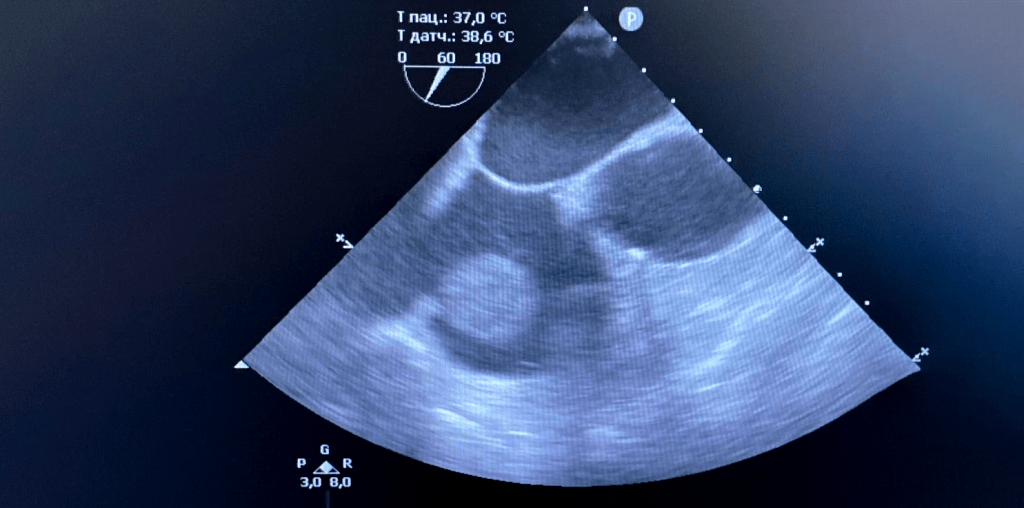

Эхокардиографическое изображение редкого случая миксомы нетипичной локализации – опухоль на ножке располагалась на границе правого предсердия и устья нижней полой вены. Больной успешно прооперирован в КВМТ им. Н.И. Пирогова СПбГУ в условиях искусственного кровообращения, кардиоплегии и гипотермической остановки кровообращения.

• Эхокардиография (трансторакальная и чреспищеводная) – основной и наиболее доступный метод диагностики опухолей сердца. В абсолютном большинстве случаев предоставляет достаточно информации об образовании и наиболее оптимальном способе его лечения.